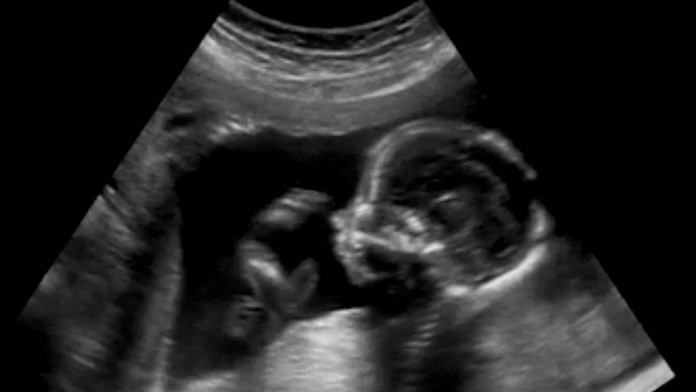

Ilustračná snímka Zdroj: shutterstock.com

Príbeh Nancy Davisovej (36) poznajú už takmer celé Spojené štáty americké. Mladá matka troch detí je štvrtýkrát tehotná, ale tentoraz sa šťastného pôrodu nedočká. Lekári diagnostikovali jej ešte nenarodenému dieťaťu vážnu vývojovú chybu, pre ktorú sa mu netvorí lebka.

Rodičia sa musia zmieriť s tým, že ich dieťa mimo tela matky neprežije. Lekári odporučili potrat, ale v štáte Louisiana jej ho nikto nechce vykonať. Platí tu totiž prísny potratový zákon.

„Nosím to dieťa iba preto, aby som ho potom pochovala,“ prezradila zúfalá žena denníku The New York Times. Plod trpí vzácnym ochorením, s ktorým odborníci nedokážu nič urobiť. Matke to oznámili v desiatom týždni tehotenstva. Odporučili jej okamžitý potrat, ale nastali komplikácie.